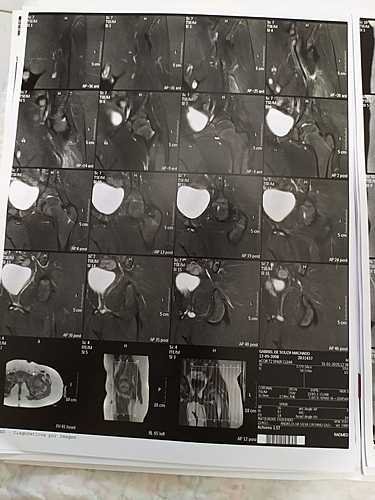

Gabriel De Souza Machado Tem 11 Anos E Devido A Dor E Inchaço Na Perna No Dia 29/01/2020 Fez Um Raio-X Que Detectou Um Tumor Na Perna Esquerda Com 17cm. Outros Exames Foram Feitos E Dia 03/02/2020 Infelizmente Foi Confirmado Um Câncer. Mais Exames Estão Sendo Feitos E Tomografia,Cintilografia, Biópsia. Porém Esses Exames Estão Sendo Feitos Em Minas Gerais Onde Será Dado Inicio Ao Tratamento. Nesse Momento Além Dos Gastos Com Os Primeiros Exames Estamos Tendo Muitos Gastos Com Transporte, Hospedagem E Alimentação. Agradecemos A Todos Que Puderem Ajudar, Não Só Com As Doações Mas Também Orações E Compartilhamento Para Alcançarmos Mais Pessoas

Gabriel De Souza Machado is 11 years old and due to pain and swelling in his leg on 29/01/2020 he underwent an X-ray that detected a 17cm left leg tumor. Other exams were done and on 03/02/2020 Unfortunately a cancer was confirmed. More Exams Are Being Taken And Tomography, Scintigraphy, Biopsy. However, these exams are being done in Minas Gerais where treatment will begin. At this moment, in addition to the expenses with the first exams, we are having many expenses with transportation, accommodation and food. We thank everyone who can help, not only with donations but also prayers and sharing to reach more people